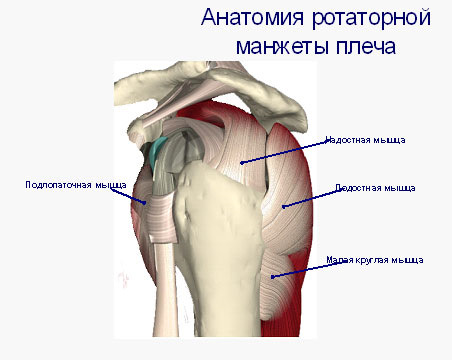

Фотографии мышц ротаторной манжеты плеча